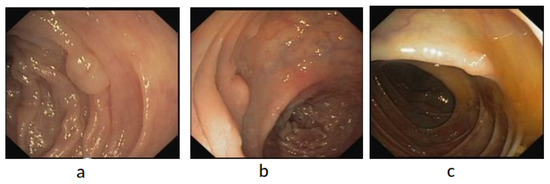

4.4.3. Visualization of Detection Results